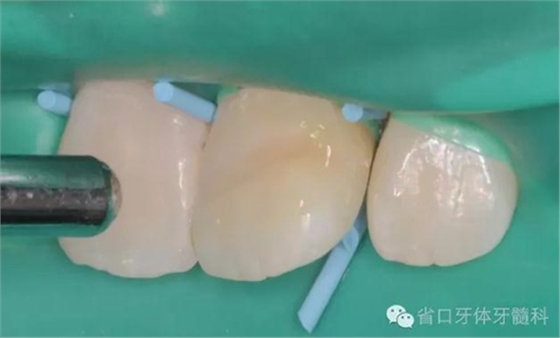

斷冠粘接前試對(duì)接

DUO-LINK樹脂水門汀(BISCO)對(duì)位粘接,(牙齦紅腫,沒有安放橡皮障)

光固化,去除多余樹脂水門汀,近中鄰面洞和舌側(cè)開髓孔樹脂充填,拋光,調(diào)整咬合。